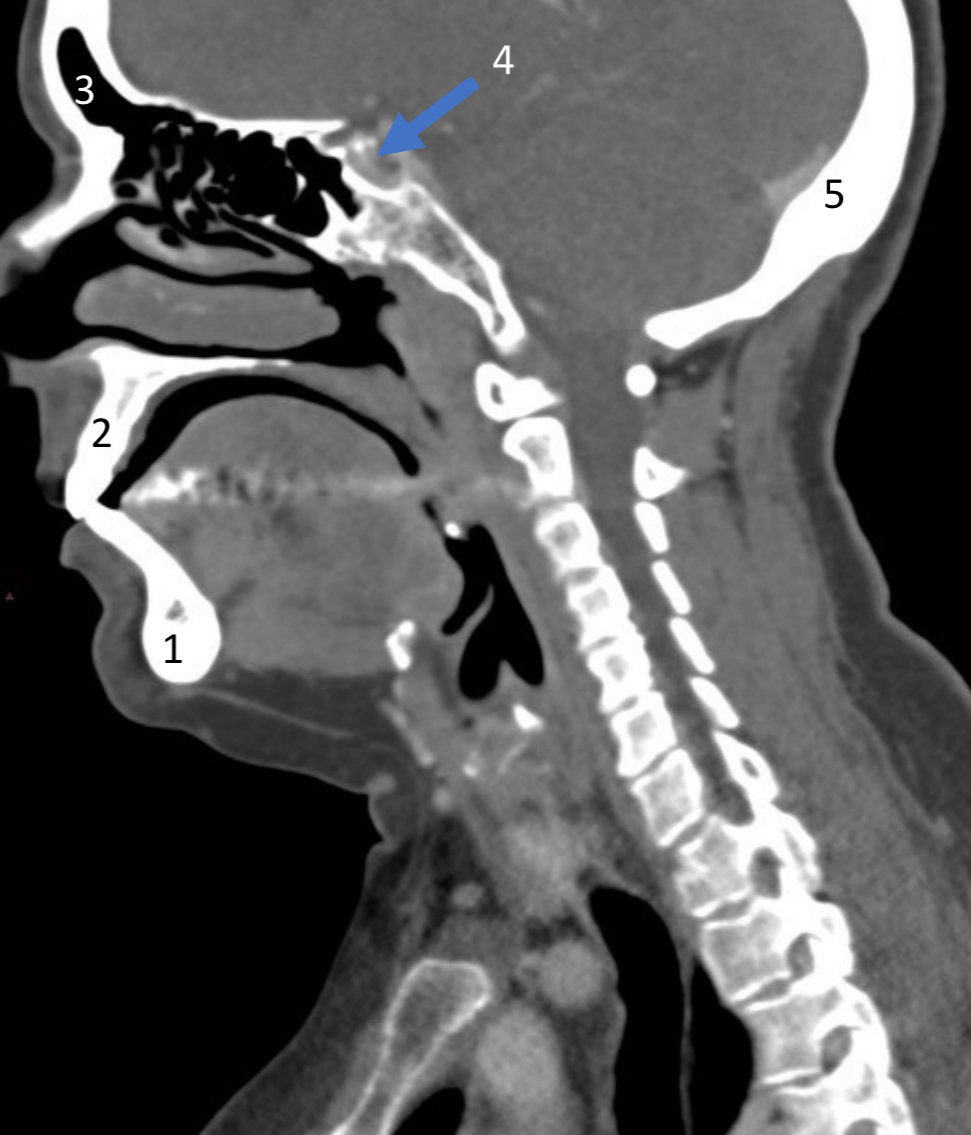

Mandible

ID bone

Maxilla

ID bone

Frontal sinus

ID structure

Pituitary fossa

ID structure

Occipital

ID bone

Lambdoid suture

ID structure

Frontal sinus

ID structure

Orbital margin

Orbit

Maxillary sinus

ID structure

Mandibular condyle

ID structure

Inferior nasal concha

ID structure

Hard palate

ID strucutre

Gonial angle

ID strucutre

Petrous ridge

ID structure

Groove of middle meningeal a.

ID structure

Roof of orbit

ID structure

Frontal sinus

ID structure

Pituitary fossa

ID structure

Petrous ridge

ID structure

Sphenoid sinus

ID structure

Hard palate

ID structure

Mastoid air cells

ID structure

Zygomatic arch

ID structure

Mandibular condyle

ID structure

External auditory meatus

ID structure

Mastoid air cells

ID structure

Foramen magnum

ID structure

Foramen ovale

ID structure

Foramen spinosum

ID structure